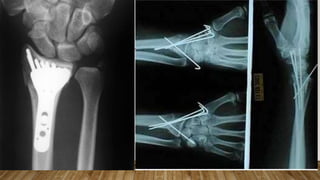

This document discusses radiology and the use of x-rays. It begins with an introduction to radiology and x-rays, noting their importance as the "father of medical investigations." It then discusses anatomy as seen on radiographs and whether x-rays are enough. The document goes on to compare gross views to radiological views, noting what each can and cannot show. It highlights important figures in the development of radiology, from x-rays to CT, MRI, and ultrasound. Specific anatomical structures visible on upper and lower limb x-rays are listed. The document concludes by discussing how pathologies appear on x-rays and the importance of clinical history and knowledge when interpreting radiological images.